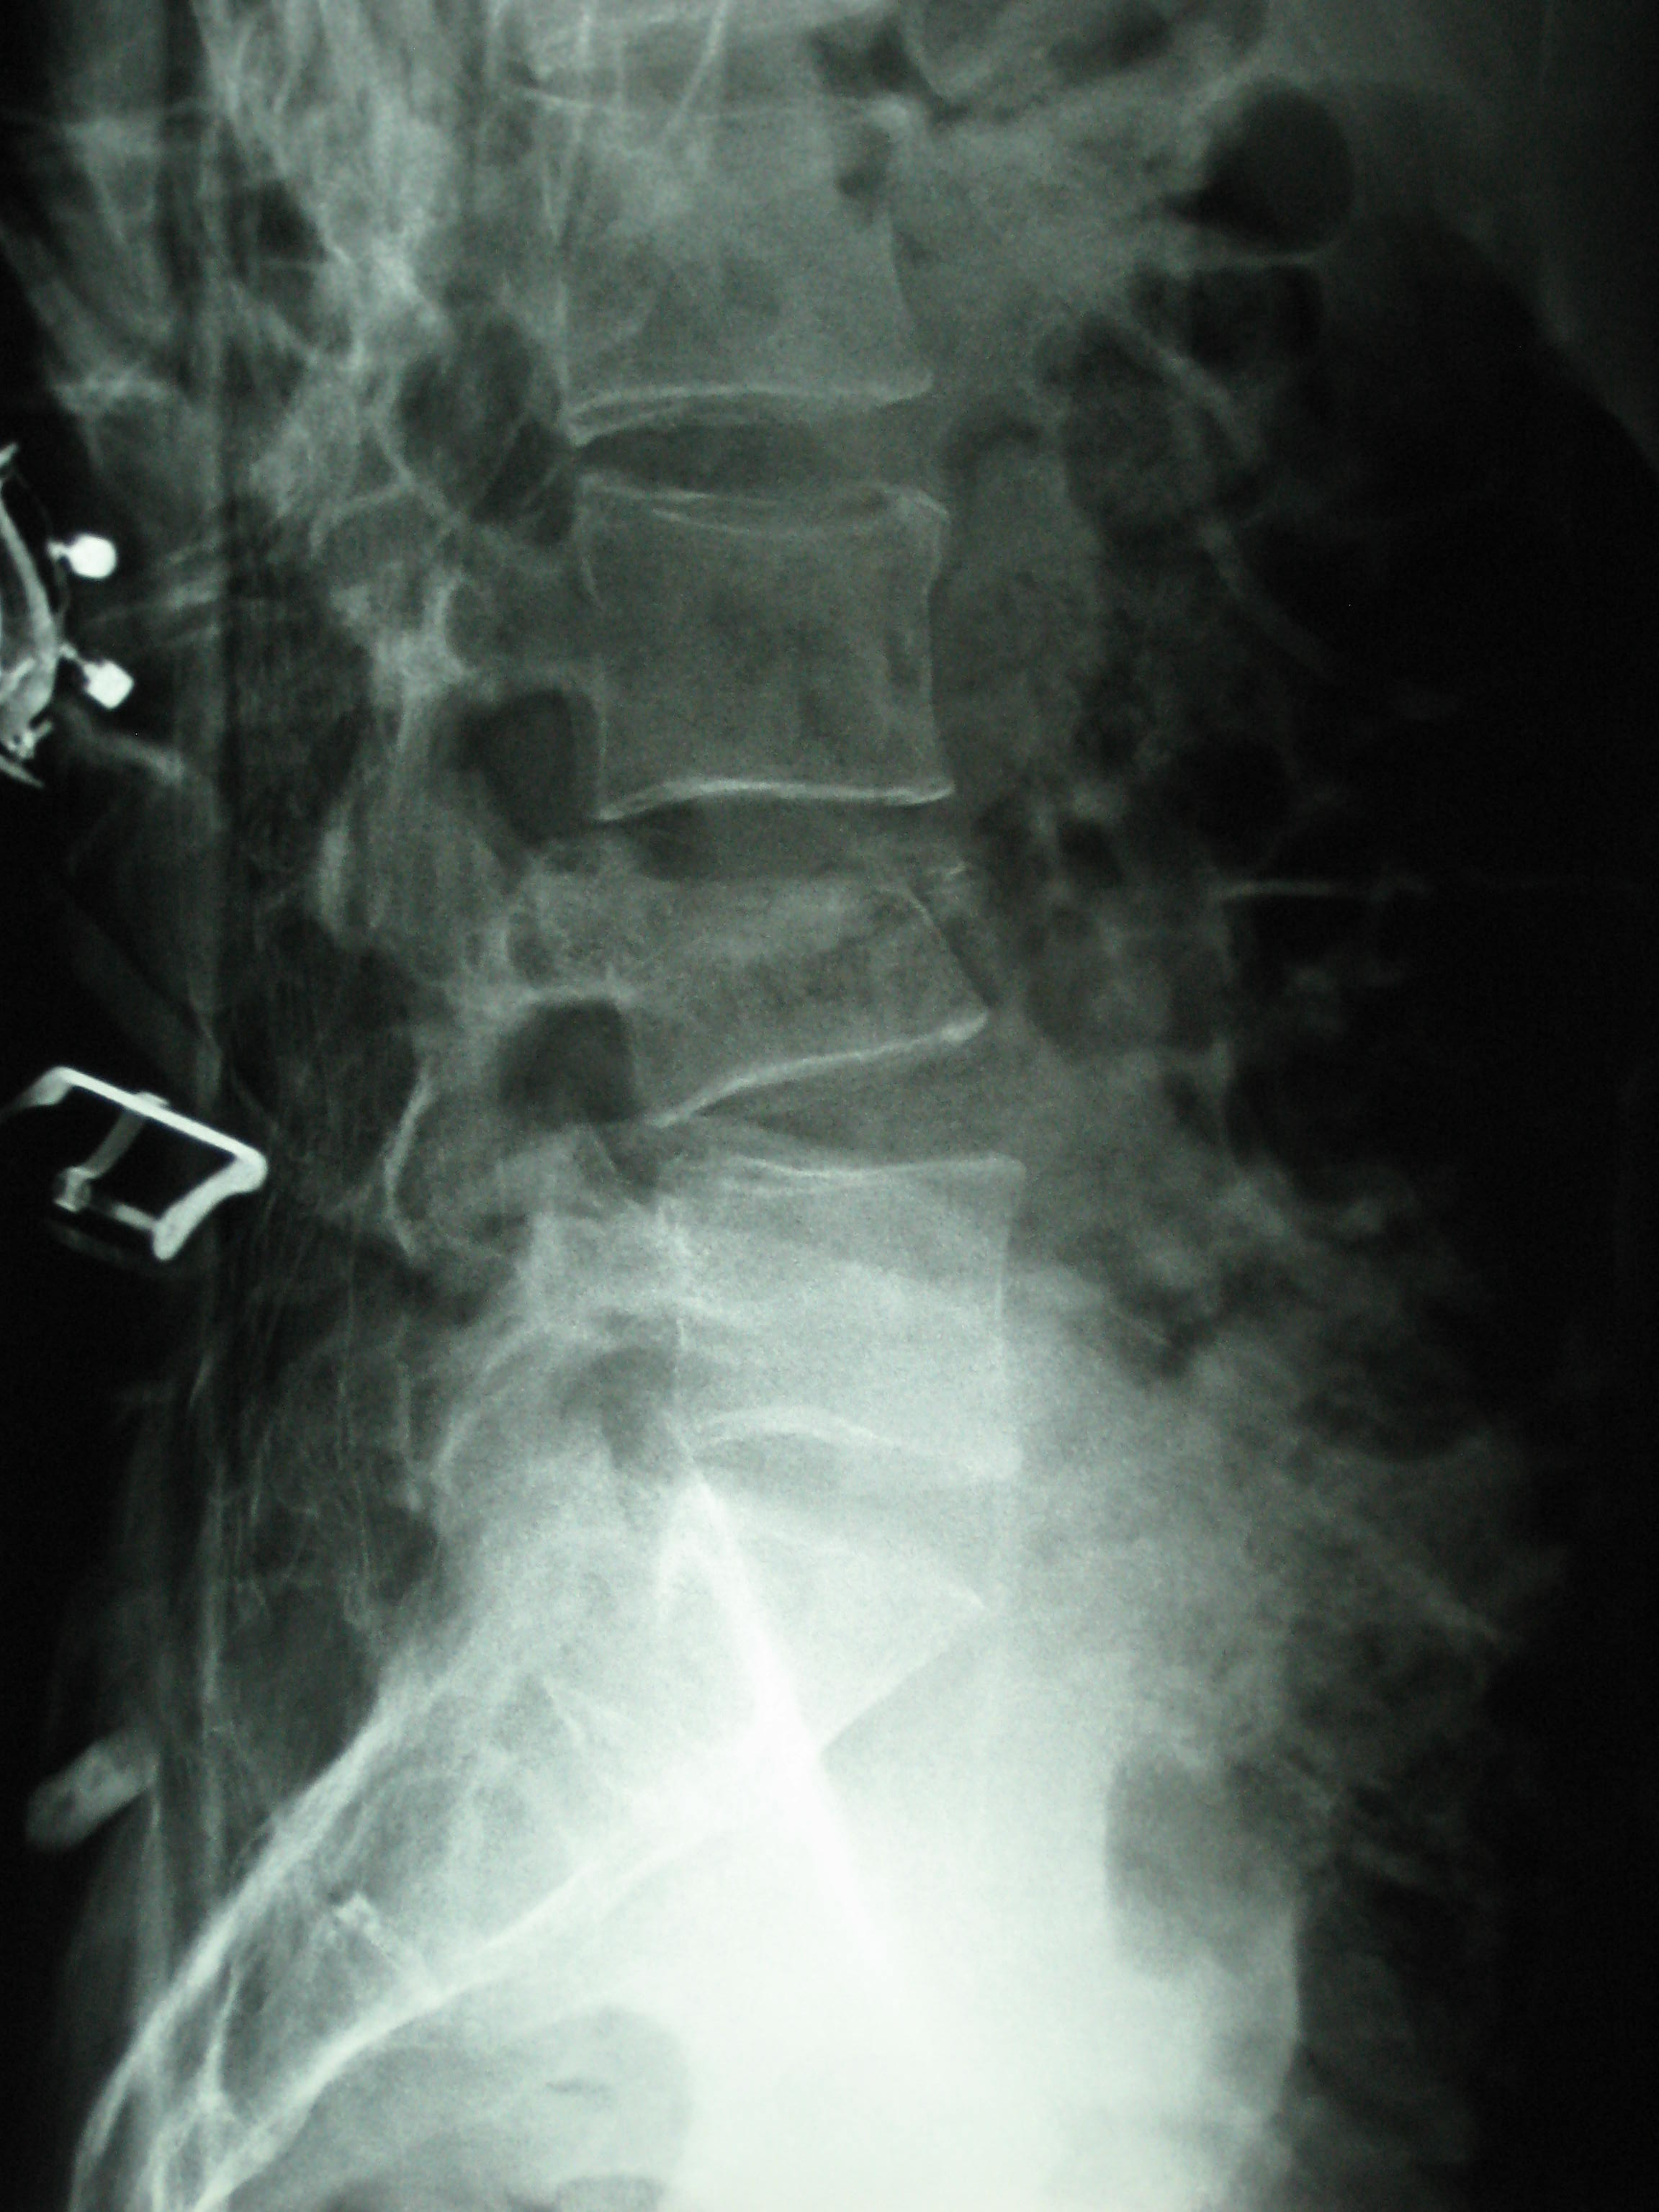

Рентгеновские снимки и медицинские изображения компрессионных переломов